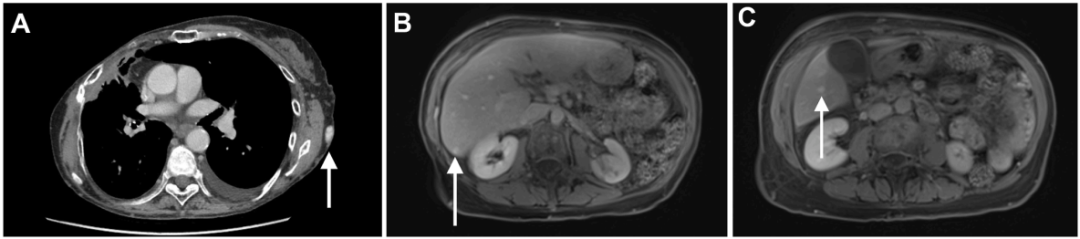

鉴于患者存在持续低白蛋白血症,且未见明确肾脏、肝脏及营养相关病因,遂行进一步检查。粪便α-1抗胰蛋白酶(A1AT)升高至356mg/dL,A1AT清除率升高至171mL/24h。胸部CT示左侧胸壁内多发血管扩张,提示可能存在血管异常(图A)。腹部磁共振成像(MRI)发现2个亚厘米级血管瘤,分别位于肝右后下缘尖端及肝右叶下段(图B、C)。

A1AT清除率检测是诊断PLE的金标准,结果证实患者存在异常肠道蛋白丢失。PLE的鉴别诊断包括胃肠道黏膜损伤、黏膜通透性增加及淋巴管阻塞。推进式小肠镜检查显示乳糜管弥漫性扩张,符合肠淋巴管扩张症表现。乳糜泻相关血清学检测阴性,小肠活检标本未见炎性浸润、上皮内淋巴细胞或绒毛异常,但可见淋巴管扩张(图G,黑色箭头)。